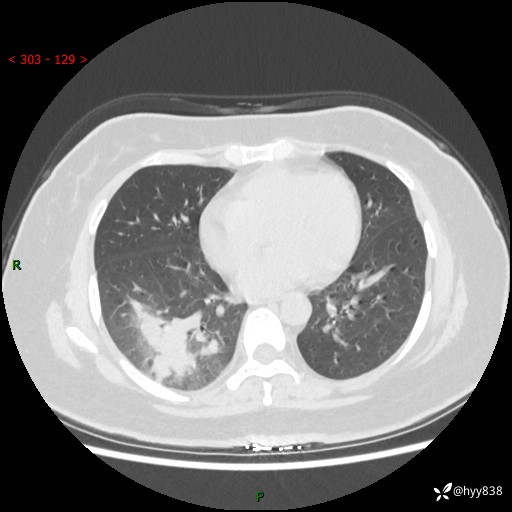

胸部CT平扫